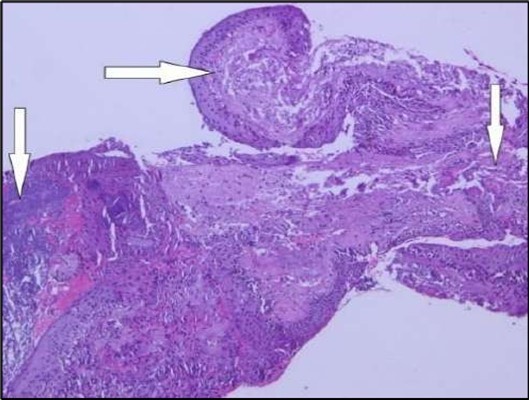

Two weeks post-surgery, the left eye showed significant healing, with a small conjunctival granuloma and vascularization at the ulcer margins. The cornea was clear with a central leading edge nasally, deep and quiet anterior chamber and clear lens. VA 6/6 bilaterally and IOP normal. Histopathology of excised conjunctiva showed non-keratinized squamous epithelium with superficial erosions, stromal elastosis, hemorrhage, and inflammatory infiltration, but no signs of granulomatous disease, malignancy, or viral evidence, findings consistent with idiopathic localized inflammatory process. The patient reported significant relief and satisfaction post-surgery, resuming normal activities. Treatment continued with oral prednisolone 25 milligrams every other day, tobramycin-dexamethasone ointment twice daily, and preservative-free artificial tears four times daily Figure 4, Figure 5a, Figure 5b, Figure 5c, Figure 5d.

Figure 5a.OS, Hematoxylin and eosin (H&E) stained section of the corneal specimen demonstrating full-thickness epithelial loss with underlying stromal necrosis.

Histopathological examination revealed a dense infiltration of CD138-positive plasma cells within the excised conjunctival tissue (Figure 5b, Figure 5c, Figure 5d). This finding supports an antibody-mediated immunopathogenesis in Mooren’s ulcer, consistent with Type II and Type III hypersensitivity mechanisms described in the literature 20, 21. The prominent presence of CD138- positive plasma cells provide a clear pathological rationale for conjunctival resection, as excision of the immunologically active perilimbal conjunctiva effectively removes the local 'factory' of autoantibodies that drive corneal stromal destruction, thereby halting ongoing tissue damage 21.